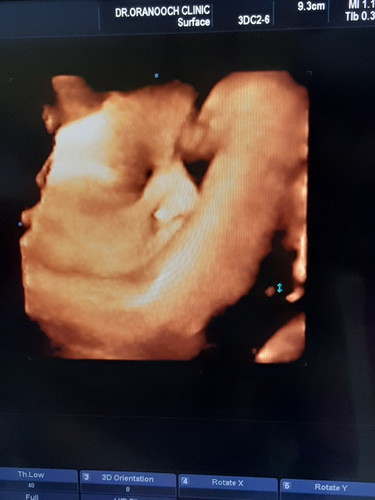

33วีคคับ

วันนี้ได้เห็นน้องชัดค่ะ แต่เสียดายเอาแขนปิดหน้าไปนิด แม่มีเรื่องอยากถามแม่ๆๆว่า มีใครเคยเป็นแบบนี้บ้างไมค่ะ คุนหมอบอกว่าลูกอัณฑะของลูกชายมีน้ำยุด้วย หมอบอกไม่อันตรายอะไรจะหายได้เองเกิดขึ้นได้ในเด็กแรกเกิด แต่ก็อดห่วงอดคิดไม่ได้ ลูกๆๆๆใครเคยเป็นบ้างไมค่ะ จะหายเองจริงรึป่าวค่ะ แชร์ประสบการณ์ให้ฟังหน่อยค่ะ ขอบคุณค่ะ

หม่าม๊า of 1 สุดหล่อ คุณชาย